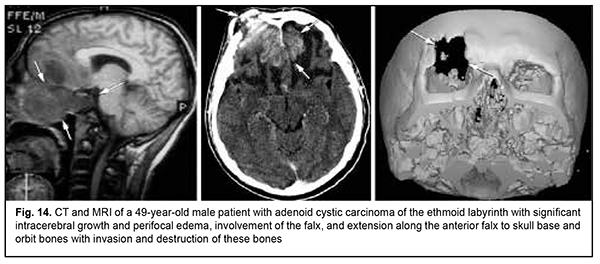

Keratinized squamous cell carcinoma and non-keratinized squamous cell carcinoma are similar in their course and grow locally. Their intracranial growth is mild (Figs 11, 12). Adenoid cystic carcinoma is a highly differentiated cancer that commonly grows locally at the site of origin. The tumors grow expansively (Fig. 13), and may extend intracranially and intracerebrally. Adenocarcinomas are malignant tumors of the lacrimal and salivary glands and paranasal sinuses characterized by early intracerebral invasion with an aggressive course. Fig. 14 shows the adenocarcinoma of the ethmoid labyrinth with significant intracerebral growth and perifocal edema, involvement of the falx, and extension along the anterior falx to skull base and orbit bones with invasion and destruction of these bones.